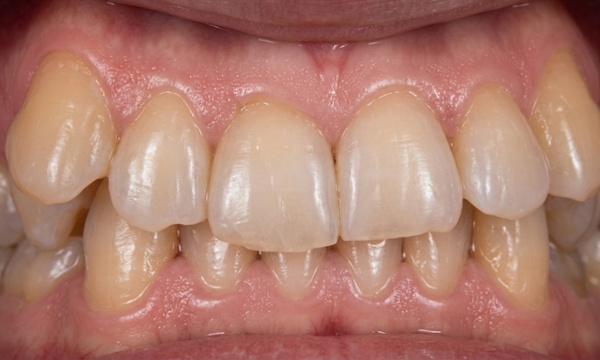

Orthodontic treatment for adults often involves managing complex dental histories. This patient in his 40s presented with a collapsed, square-shaped maxillary arch, a crossbite, and shifted midlines. Complicating the case were congenitally missing lower second premolars and over-retained primary first molars. Under the specialized care of Dr. Jesus Martinez, we utilized Rapid Palatal Expansion (RPE) to restore proper arch width and traditional braces to correct the alignment and bite. Strategic management of the primary teeth and missing permanent teeth allowed us to achieve a stable, functional result secured with fixed retainers. We invite you to schedule a personal evaluation at our concierge Miami or Kendall offices, where the specialist evaluates every case personally from start to finish.